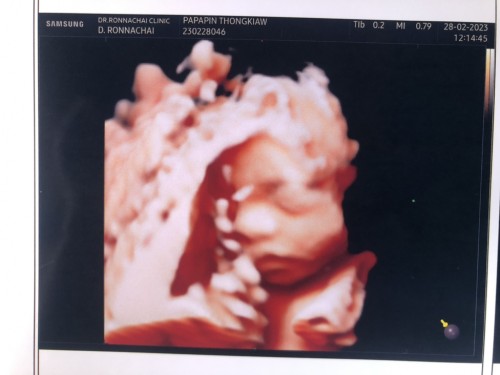

บ้านนี้26+1วีคน้องหนัก907กรัมลุงหมอบอกว่าน้ำหนักกำลังดีเลยค่ะ ทีมสูกสาวค่ะ

VIP Parentsบ้านนี้26+1วีคน้องหนัก907กรัมลุงหมอบอกว่าน้ำหนักกำลังดีเลยค่ะ ทีมสูกสาวค่ะ